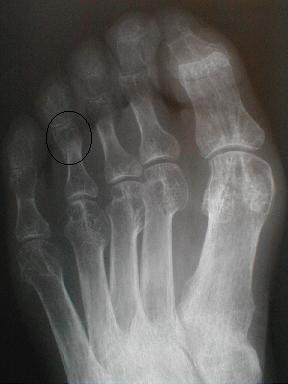

7月19日整復固定後のx-p

10月6日 受傷後96日目